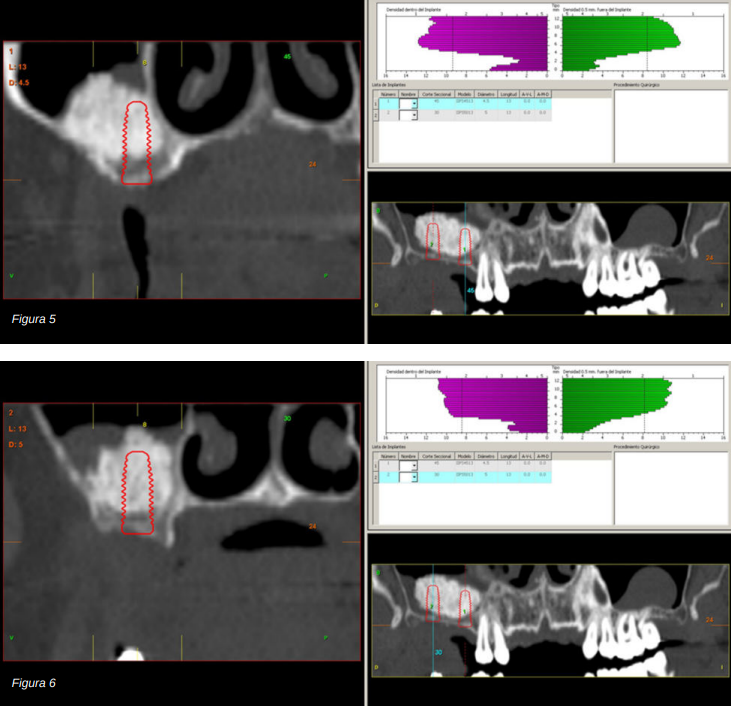

Por ello, se decide llevar a cabo una elevación de seno utilizando biomaterial (hidroxiapatita bovina) unido a PRGF-Endoret. Se realiza la elevación y tras cinco meses se procede a la evaluación de un nuevo Cone-beam dental para poder visualizar la cantidad y calidad del injerto obtenido para la inserción de los implantes dentales. En los cortes correspondientes a los molares del primer cuadrante podemos observar una perfecta consolidación del injerto con la posibilidad de insertar implantes de 13 mm.

En el año 2007, con los implantes cortos sin pleno desarrollo y sin estudios que demostraran la importancia del diámetro frente a la longitud del implante el protocolo terapéutico para estos casos era muy diferente (Figuras 5-7), centrándose los esfuerzos en la búsqueda de un anclaje por longitud del implante en lugar de buscar la estabilidad bicortical (vestibular-lingual) que realizan los implantes cortos y anchos. Durante este tiempo se produce también

Transcurridos cuatro años, los molares del segundo y tercer cuadrante comienzan a tener una movilidad excesiva y problemas periodontales graves, por lo que se decide la extracción de los mismos y la regeneración de los alveolos con PRGF-Endoret. Una vez regenerada la zona (mes y medio después) se procede a la obtención de un Cone-beam para evaluar el volumen óseo residual. En el mismo se puede observar cómo existe una cresta ósea desigual con zonas de 3,3 mm de altura hasta 7 mm como máximo (Figuras 9 y 10). En esta ocasión, debido al cambio de protocolo descrito anteriormente, se opta por la inserción de implantes extra-cortos de forma directa, ya que los protocolos quirúrgicos para abordar este tipo de situaciones en el año 2011 variaron sustancialmente, siendo estos implantes una herramienta de primera línea para el tratamiento de este tipo de atrofias (Figura 11). Se seleccionan dos implantes extra-cortos (5,5 mm de diámetro x 6,5 mm de longitud para la pieza dental número 26 y 6 mm de diámetro por 5,5 mm de longitud para la pieza dental número 27).